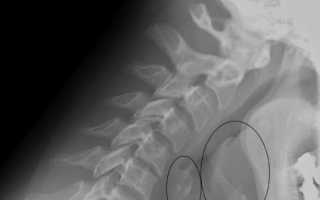

Томограмма на глубине 30 мм четко выявляет черпалонадгортанные связки, которые могут быть смещены или деформированы при раке гортани. Сложнее диагностировать хрящевую ткань, которая не находится в стадии обызвествления.

Томографическое исследование при 40 мм показывает пластинки щитовидного хряща и ширину просвета гортаноглотки. Рентгеновское изображение ЛОР-структур в стадии окостенения показывает состояние дна грушевидного синуса. Рационально такое обследование для следующих групп пациентов:

Из-за низкой эффективности рентгенографии ЛОР-образований классическая рентгенография в прямой и боковой проекциях не приносит положительного эффекта. Чтобы исключить патологические изменения органа, ее дополняют другими методами – фиброларингоскопией или томографией.